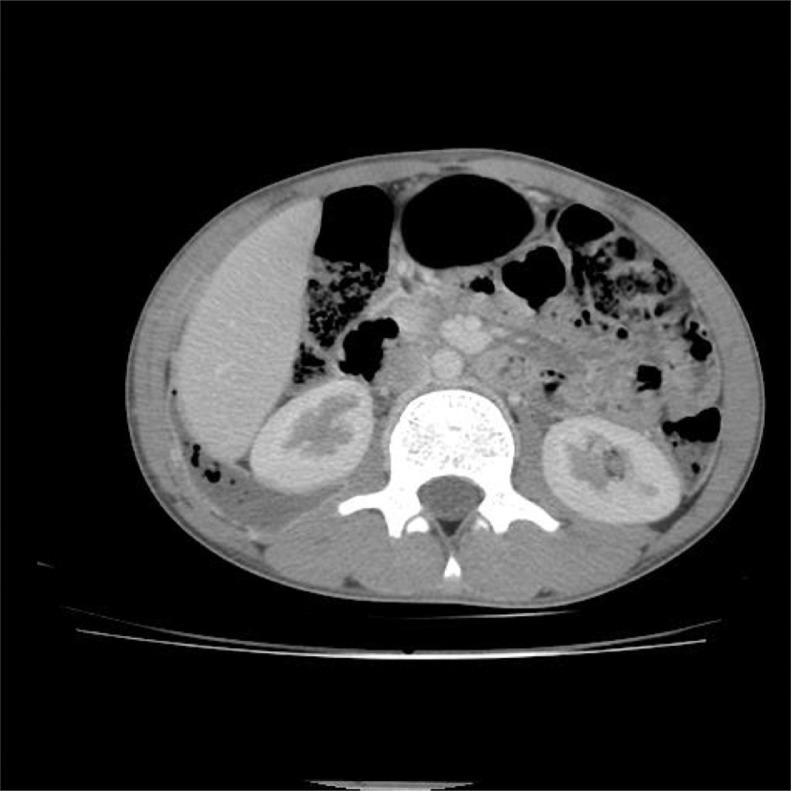

Retrocecal appendicitis usually presents with atypical signs and symptoms which may lead to delayed diagnosis, perforation and serious complications. Development of a large lung abscess secondary to perforation of retrocecal appendicitis in an adolescent patient is an extremely rare entity and to the best of our knowledge has not been described in literature. We present a 15-year-old boy with complaint of chest pain, cough, fever, vague abdominal pain and raised inflammatory markers who underwent CT examination. On CT, a collection with focal calcification was noted in the right iliac fossa that extended along the right retroperitoneum through the retrocrural space in the right lung base communicating with a cavitary pulmonary lesion with air-fluid level. A diagnosis of perforated retrocecal appendicitis with retroperitoneal and right lung abscesses was made. The patient underwent appendectomy and the entire retroperitoneal and lung abscesses were drained. A lung abscess as a complication of perforated retrocecal appendicitis should be in consideration in septic patients with thoracoabdominal infectious manifestations.